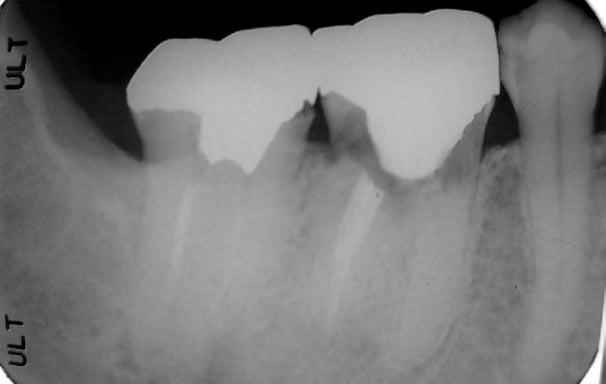

Consiste en identificar la causa del dolor en un diente, ya sea por caries, infecciones u otras afecciones. Se realiza mediante exámenes clínicos, radiografías y pruebas de sensibilidad.

Se revisa si hay fracturas en la parte visible del diente. Las fracturas de la corona pueden ser causadas por trauma o caries extensas y pueden afectar el tratamiento endodóntico.

Evaluación de fracturas de la corona

Se identifica si hay fracturas en la raíz del diente, que pueden causar dolor, infecciones o problemas de estabilidad dental. Se utilizan radiografías y exámenes clínicos para este diagnóstico.

Evaluación de fracturas radiculares

Diagnóstico de reabsorción radicular

Incluye visitas posteriores al tratamiento para evaluar la recuperación del diente y asegurarse de que el tratamiento haya sido exitoso. Se revisan radiografías y se realiza un examen clínico.